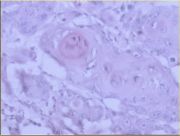

| 2021年12月10日 (五) 13:16 | 16号切片-鳞癌(癌巢)-镜下观2.jpg (文件) |  |

62 KB | Cirno.9 | 基于MsUpload的文件上传 | 1 |

| 2021年12月10日 (五) 13:16 | 16号切片-鳞癌(癌巢)-镜下观1.jpg (文件) |  |

180 KB | Cirno.9 | 基于MsUpload的文件上传 | 1 |